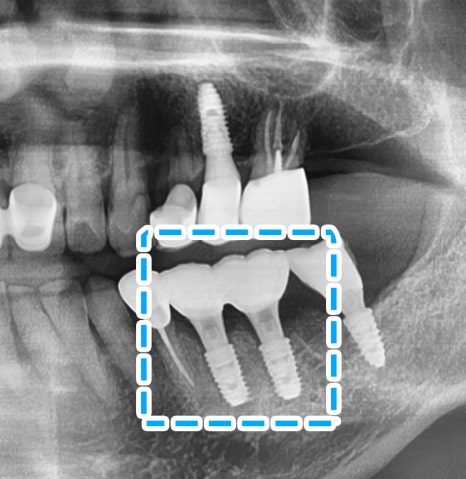

【 픽스처 식립 완료 】

계획된 위치와 각도에 맞춰

픽스처를 식립해줍니다.

이제 잇몸뼈(치조골)와 잘 붙기를 기다립니다.

뼈이식까지 함께 진행했기 때문에

회복 기간은 4개월이 걸렸는데요.

안정감있게 잘 고정되었기에

구강 내부를 본뜨고

기공소에 최종 보철물 제작을 요청합니다.